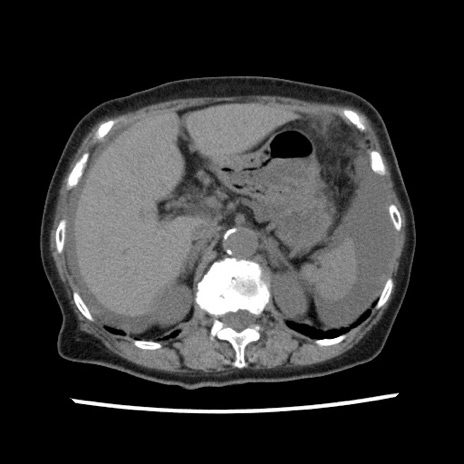

【症例】80歳代女性

【主訴】腹痛

【現病歴】8時間前から腹痛あり来院。

【既往歴】糖尿病、脂質異常症、子宮体癌にて子宮全摘術

【身体所見】意識清明・会話良好だが腹痛で苦悶様、全腹部にわたって反跳痛と圧痛あり

【データ】WBC 13600、CRP 0.14、LDH 224、CK 90